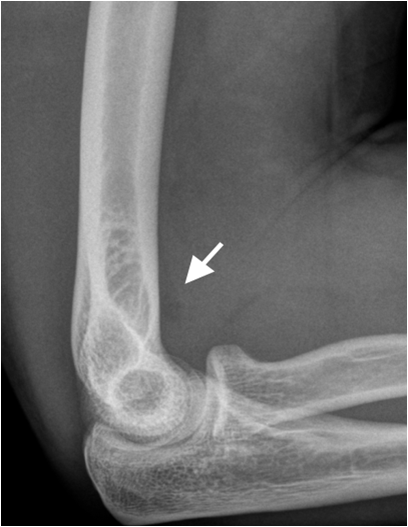

Fig. 3. Split fracture of the radial head. The fracture is clearly seen on the oblique image (right image) whereas the fracture is almost invisible on the lateral view (left image). The displaced fat pad (white arrow) indicates joint effusion and is an indirect sign of significant trauma.